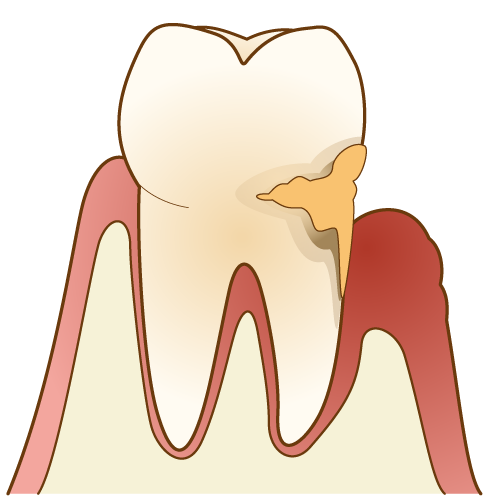

⑥ 前回詰めた綿花の状態を確認して、良い状態なら、「根管充填剤」(マスターポイント・アクセサリーポイント)というお薬を、余分な空間がないように根っこに詰めます。

⑥ 前回詰めた綿花の状態を確認して、良い状態なら、「根管充填剤」(マスターポイント・アクセサリーポイント)というお薬を、余分な空間がないように根っこに詰めます。 Q1.痛みはありますか?

Q1.痛みはありますか? ② 次に、「根管長測定器」という機械を使い、根っこの長さを正確に測ります。

② 次に、「根管長測定器」という機械を使い、根っこの長さを正確に測ります。

⑤ 次に、仮詰めをします。

⑤ 次に、仮詰めをします。 虫歯が神経まで達して炎症を起こしているので、人によってはズキズキとした痛みを感じる方もいます(>_<)

虫歯が神経まで達して炎症を起こしているので、人によってはズキズキとした痛みを感じる方もいます(>_<)